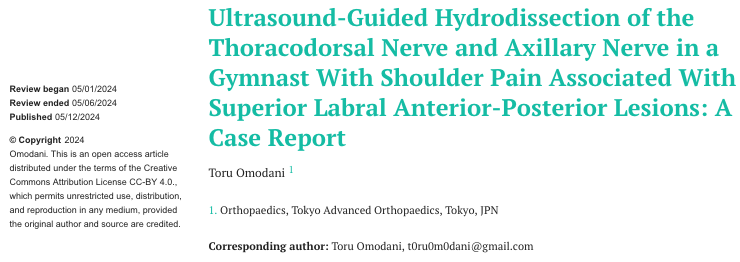

DOI: 10.7759/cureus.60157

오늘 제가 소개해 드릴 논문은

SLAP 병변이 있는 어깨 통증에서

찢어진 곳을 건드리지 않고

어깨 관절의 기능을 회복시켜서즉각적으로 통증을 해결한 최신 치료 사례입니다.** 특히 이 치료는 ‘눈으로 보면서’ 염증 유착 부위를 시술하는 바로 의 가치를 보여줍니다. > SLAP 병변, > > 단순한 구조적 문제가 아닙니다. SLAP 병변 (Superior Labral Anterior Posterior Lesion)은 주로 야구 투수나 기계체조 선수처럼**

오늘 소개해 드릴 논문은

20살 기계체조 국가대표 선수의 케이스입니다.